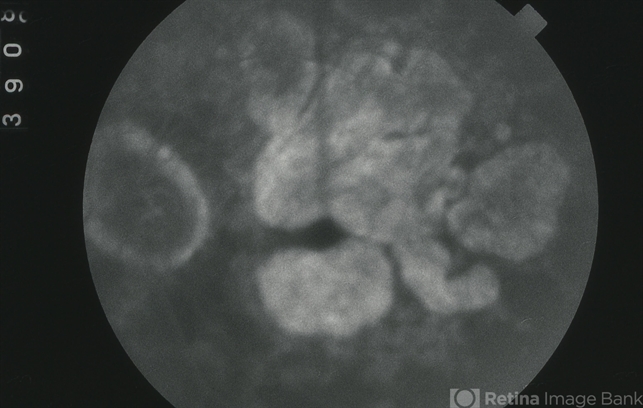

- CHORIOCAPILLARIS ATROPHY

- fluorescein angiogram (FA), FA late phase, choriocapillaris, hereditary choroidal dystrophy, hereditary choroidal atrophy

- Late-phase fluorescein angiogram image of the left eye of a 64-year-old white male with central areolar choriocapillaris atrophy showing light late staining of the central lesions OS; V.A. = 20/30